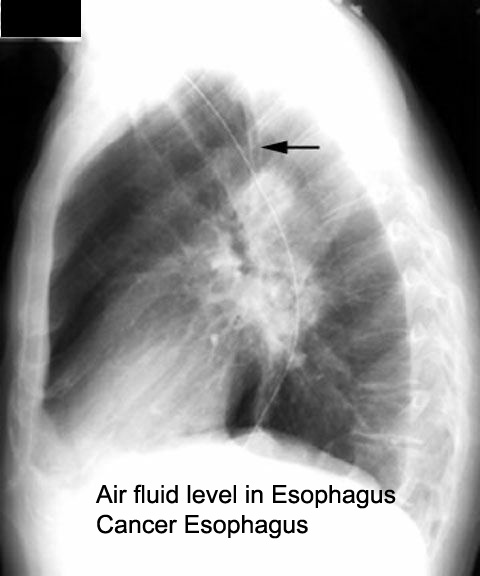

Fluid level in esophagus in lateral view

Mediastinum plastered with tumor (lateral view) with esophageal obstruction